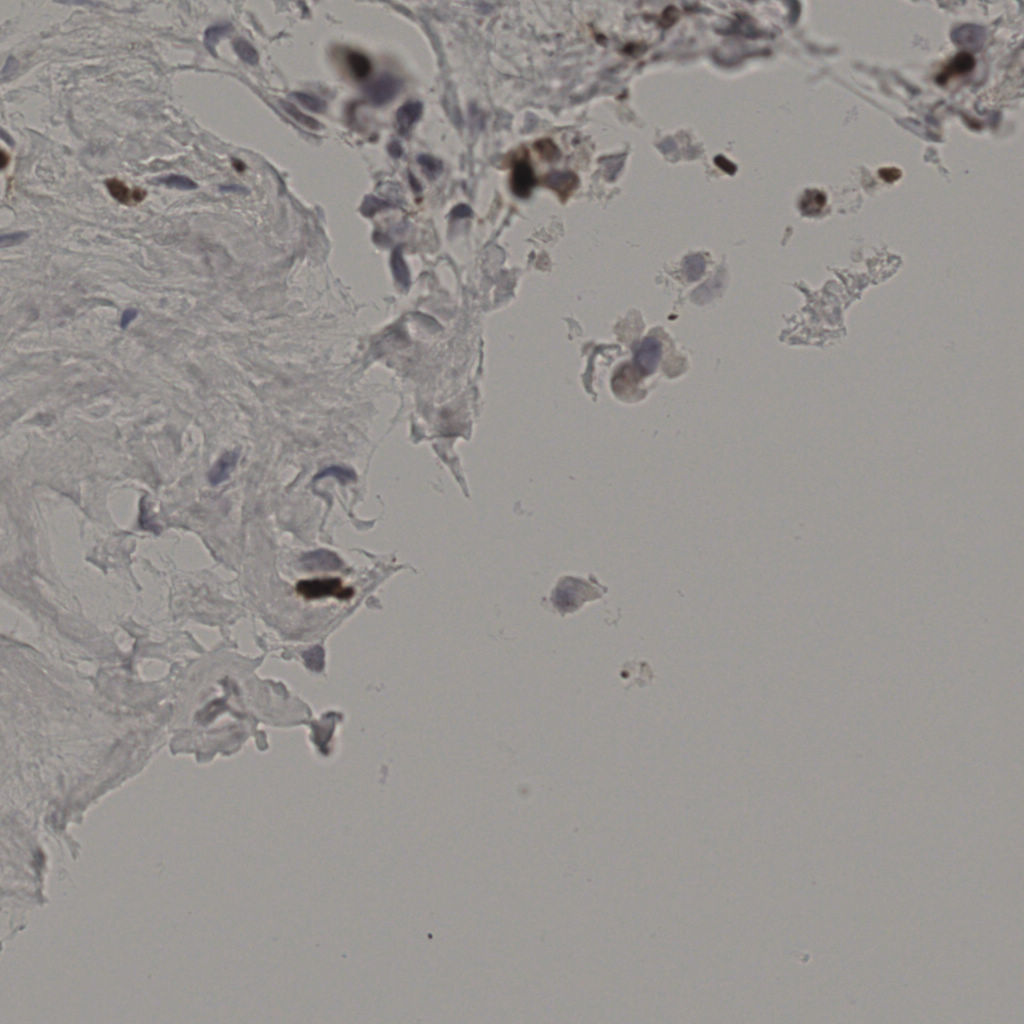

17.75%

Ki67 指数

阴 7986

阳 1723